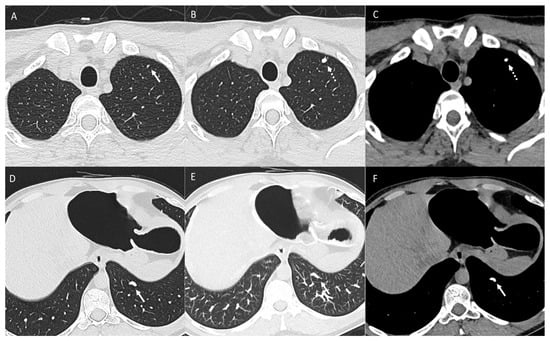

2.1. Parenchymal Metastasis

3. Pleura

4. Mediastinum and Hilum